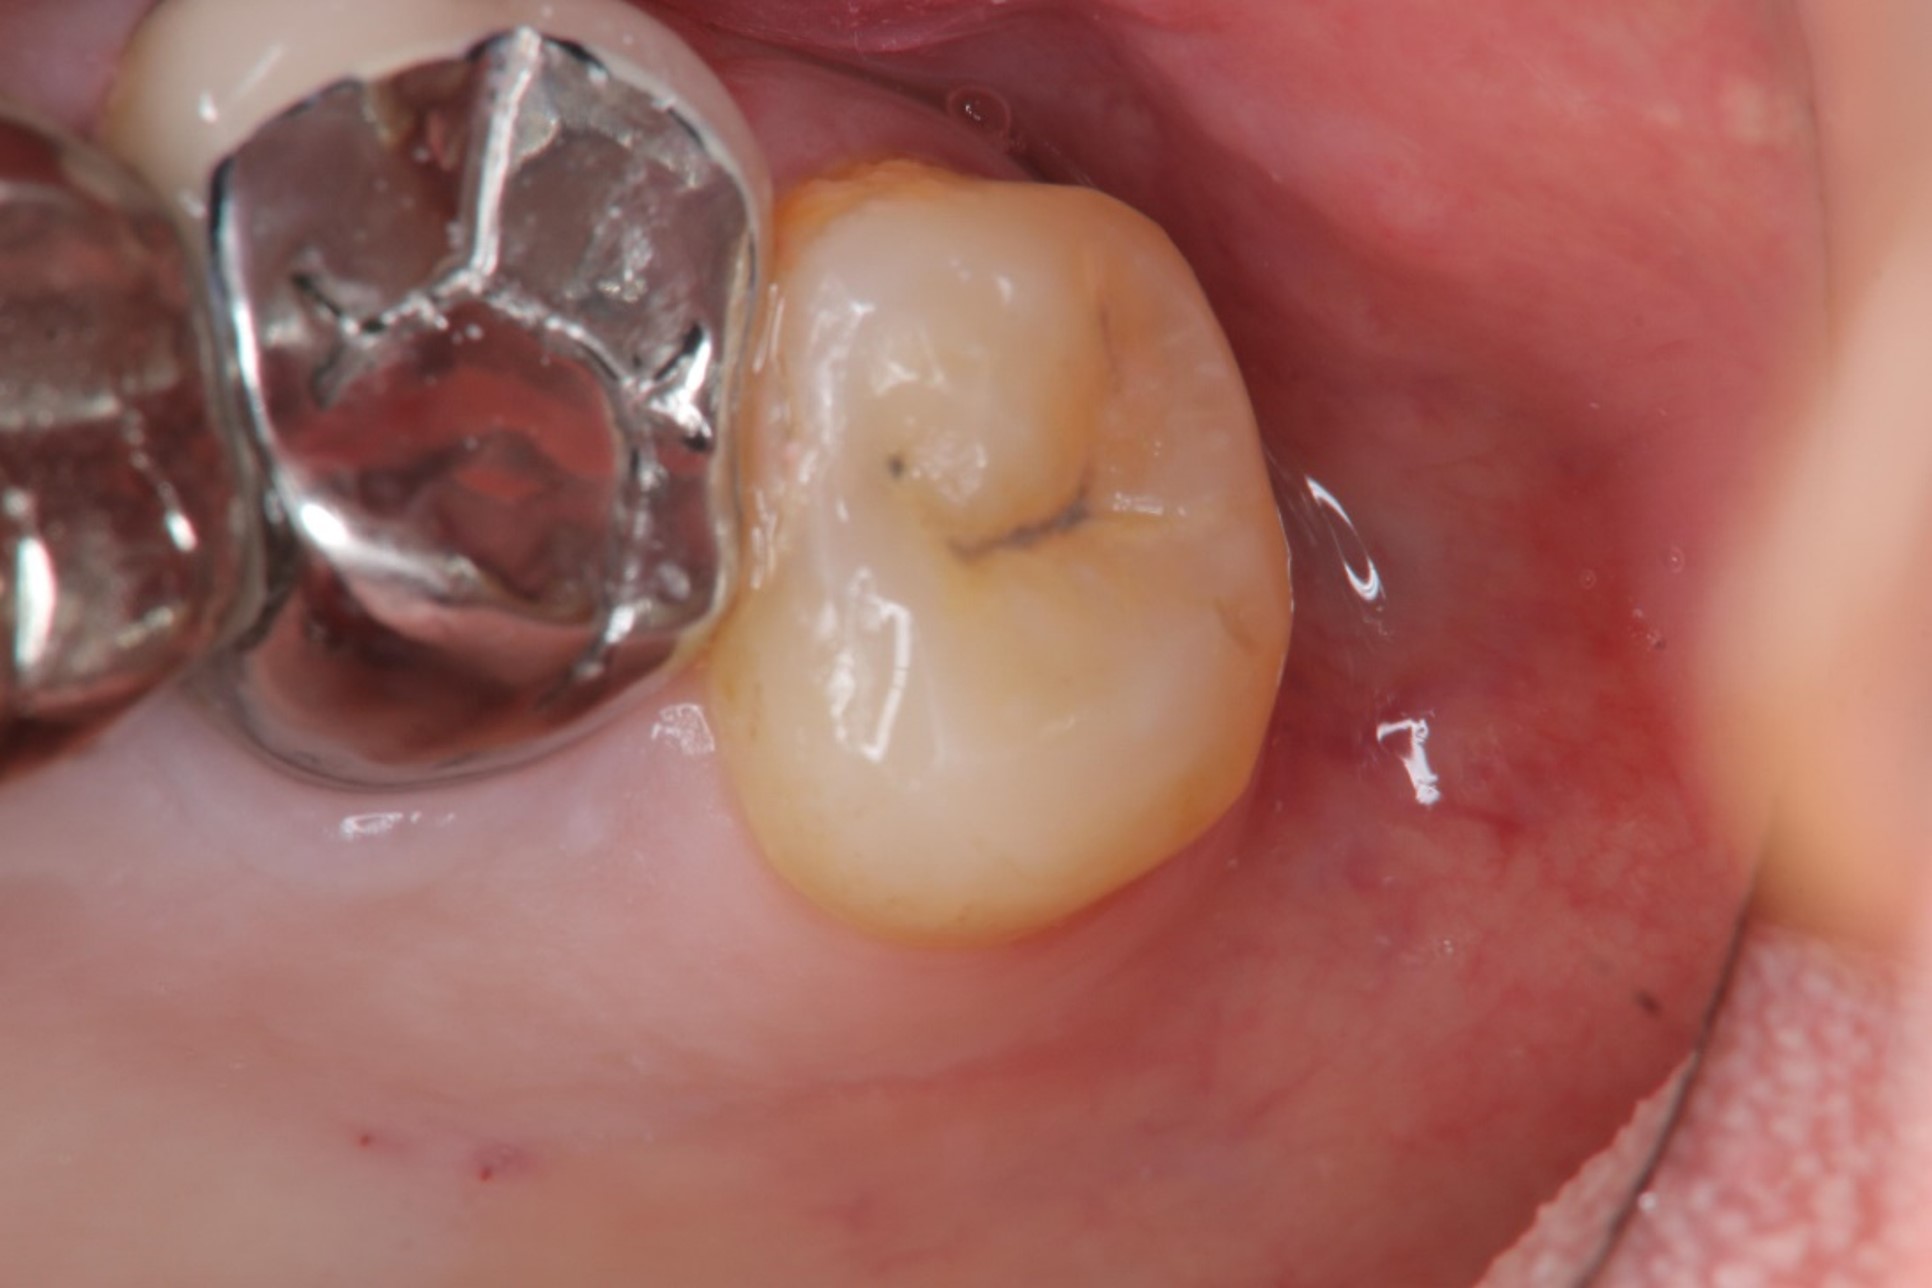

治療前,左上阻生齒深度蛀牙

微創拔除阻生齒,骨膠原修復並縫合